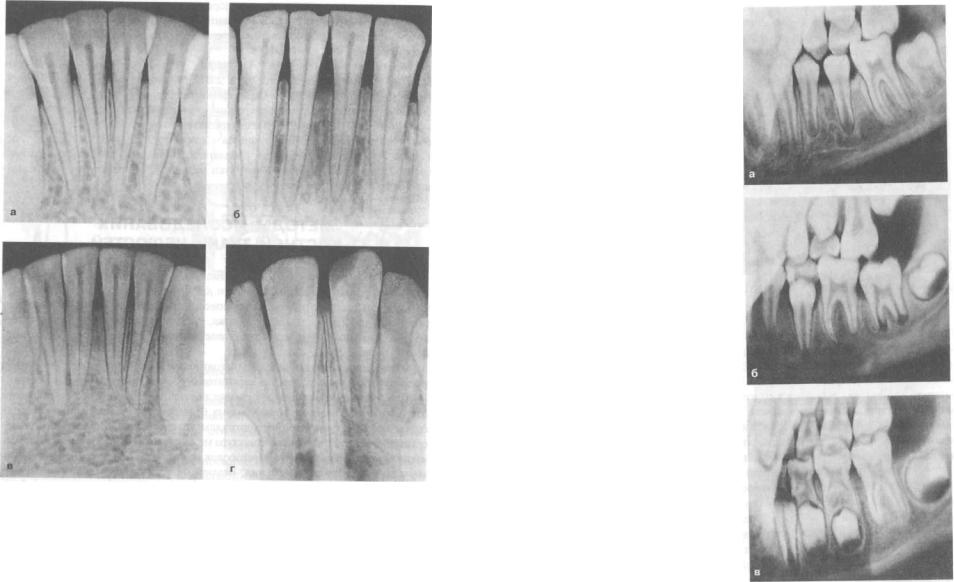

Анатомия: Межкорневая костная перегородка

Раздел: Галерея впечатлений